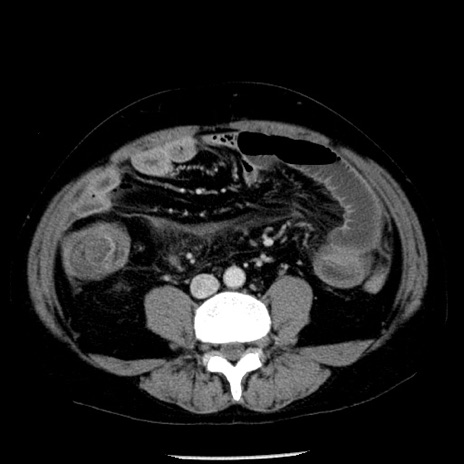

症例29(横断像)

【症例】40歳代男性

【現病歴】2日前から胃痛あり。徐々に周期的な激痛に変化した。本日になっても激痛があるため受診。

【身体所見】意識清明、BT 38-39℃台あり、腹部:膨満、やや硬、右下腹部に圧痛あり。

【データ】WBC 8500、CRP 23.26